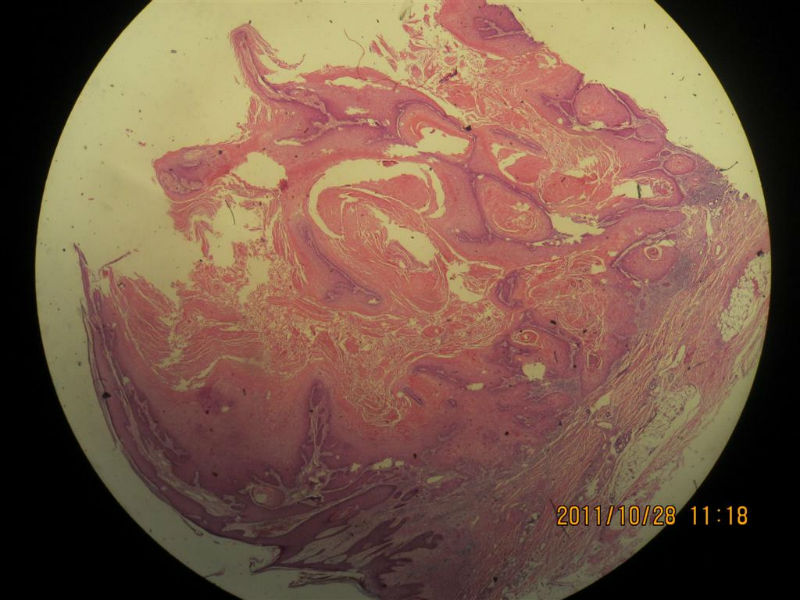

女性,71岁,右前臂肿物。角化棘皮瘤还是高分化鳞癌?

• 女性,71岁,右前臂肿物。角化棘皮瘤还是高分化鳞癌?图1

图1

• 女性,71岁,右前臂肿物。角化棘皮瘤还是高分化鳞癌?图2

图2

不知道肿物的生长速度怎样?活动度?低倍看火盆样外观、唇样边缘,底部较平整,无明显突破。更趋向于角化角化棘皮瘤。

低倍镜见表皮呈火山口样,内充满角质团块,周边上皮增生呈衣领样,底部表皮增生呈假上皮瘤样,上皮角不规则延伸至真皮,真皮大量炎细胞浸润.

低倍镜下看符合角化棘皮瘤